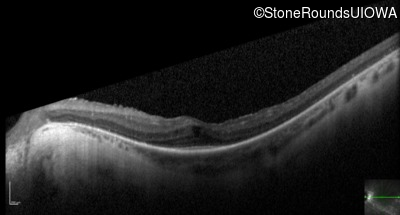

Optical Coherence Tomography - Left - 20/50 +2

Exemplar / OCT Stack

OCT Stack